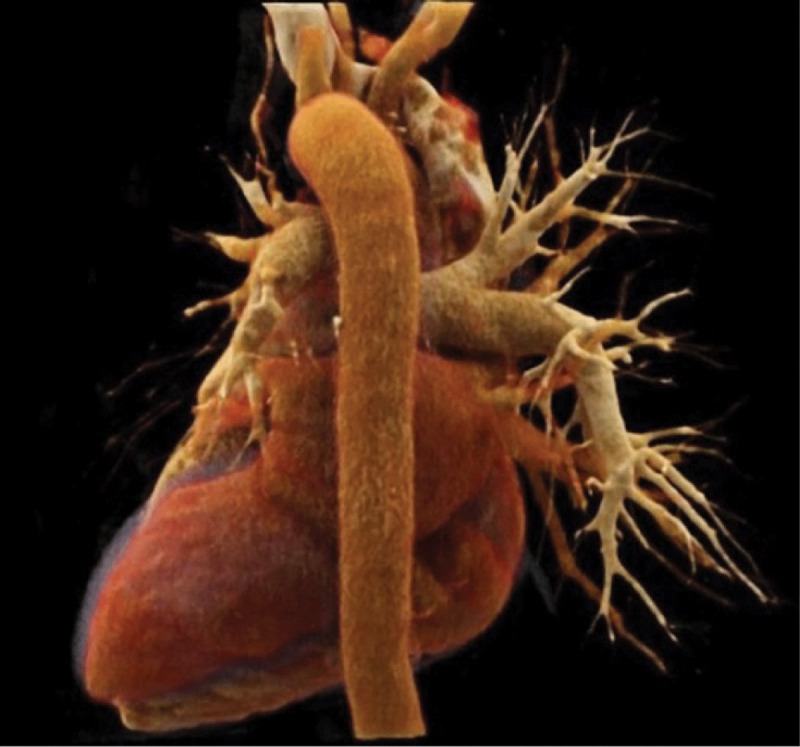

Teaching point: Description of a new radiological sign named "pulmonary hilar cavernoma" in a case of unilateral total pulmonary vein thrombosis.